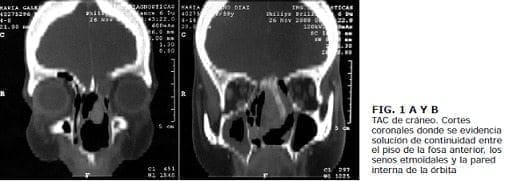

El estesioneuroblastoma no presenta un patrón definido, en los estudios de imágenes diagnósticas. Se debe sospechar al observar una lesión del tercio superior de la fosa nasal, que cause remodelación de las estructuras óseas adyacentes. Se suele observar la lesión delimitada por debajo de la lamina cribiforme. En la tomografía se observa un tumor negro intenso y brillante que causa remodelación ósea adyacente. La resonancia muestra una lesión hiperintensa en el T2. e isointensa en el T1 . que es invasora. La resonancia magnética es el estudio de elección para definir y valorar la extensión intracraneana (16).